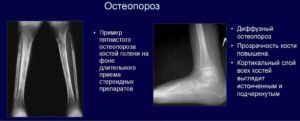

Выделяют две основных разновидности остеопороза: генерализованный (поражается вся костная система) и локальный (повышается хрупкость одной какой-либо кости). Локальный остеопороз делится, в свою очередь, на пятнистый и равномерный. Эти формы болезни отличаются распространенностью патологического процесса:

- Равномерный локальный остеопороз поражает всю кость целиком, вызывая равномерное разрежение ее структуры. Данный процесс происходит постепенно, заболевание постоянно прогрессирует. Эту форму заболевания также называют диффузной.

- Пятнистый, или очаговый, остеопороз захватывает отдельные, хаотично размещенные, участки кости. На рентгенограмме видны круглые или овальные очаги костной ткани с низкой плотностью. Пораженные сегменты могут иметь различную величину, форму и очертания. При пятнистом остеопорозе размер кости сохраняется, однако ее структура в некоторых местах становится пористой, что и приводит к излишней ломкости.